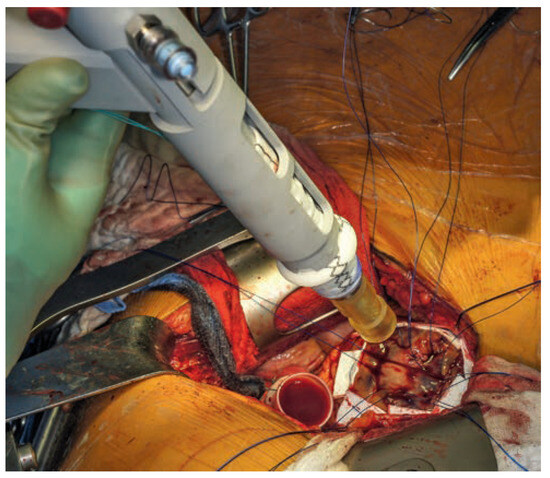

Figure 3. Pledgeted 2/0 prolene sutures for fixation of the LV-connector at the apex.

After opening the pericardium, the insertion position of the 18 mm apical connector was marked lateral to the apex. Seven pledgeted prolene 2/0 sutures were passed circumferentially through the myocardium. By means of the automated coring device, the apical connector was placed off-pump in the ventricular wall and sutures carefully tied. The coring device was removed and both conduits connected. They were secured with prolene 4/0 sutures as well as umbilical tape. The deairing clamps were released and flow initiated. Haemostasis chest tubes were inserted and thoracotomy closed in usual fashion.